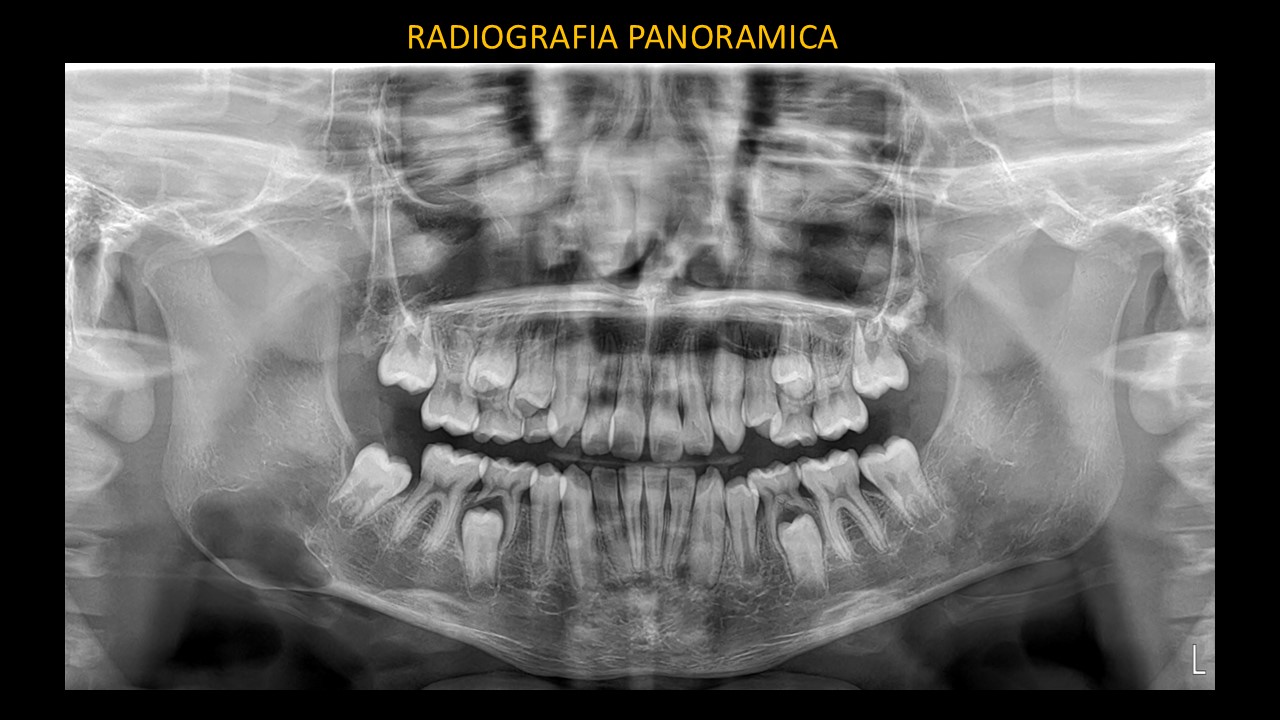

Figura 1

En la radiografía panorámica (Figura 1) se observa una imagen radiolúcida proyecta a nivel de la zona antegonial derecha.